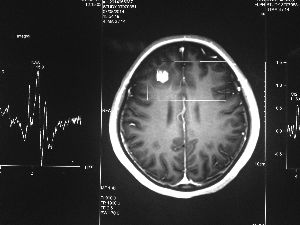

方框亮點為CT片顯示的異物

今年6月份,張敏在宿舍休息時,又發起了癲癇,也是口吐白沫,渾身抽搐。送到蘇州一家大醫院,頭顱核磁共振檢查出,張敏大腦右額葉處有一處病灶,也就是大腦額頭處有個東西。

住院前一天又發了一次癲癇